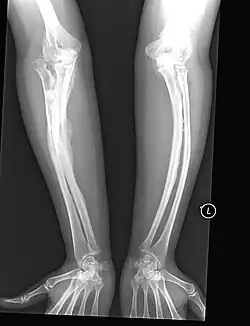

Da das Kollagen vom Typ I rund 90 % der Knochenmatrix ausmacht, ist das Hauptmerkmal der OI eine abnorm hohe Knochenbrüchigkeit. Das Synonym Glasknochen beschreibt sehr bildhaft sowohl die mechanischen Eigenschaften des wie Glas leicht zerbrechlichen Knochens als auch das Erscheinungsbild der Knochen auf Röntgenaufnahmen. Da bei der OI nur ungenügend schattengebende Knochensubstanz eingelagert ist, erhöht sich die Strahlentransparenz bei der Röntgenaufnahme, so dass der Knochen oftmals als milchglasähnliche, verwaschene Struktur dargestellt wird.